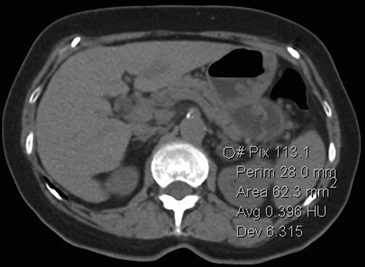

La presencia de lípidos intracelulares disminuye la densidad de la lesión debido a que estos son menos densos que el agua. El primer estudio en reportar la utilidad de la densitometría por TC en la diferenciación de una lesión suprarrenal benigna de una maligna fue el realizado por Lee et al6, utilizando la medición del coeficiente de atenuación o densidad de la lesión expresada en unidades Hounsfield (UH), en una TC no contrastada, demostrando que el coeficiente de atenuación promedio de los adenomas (2,2 UH) fue significativamente menor que la de las lesiones no adenomas (28,9 UH). Utilizando un punto de corte de 0 UH la sensibilidad de la TC no contrastada en la caracterización de un adenoma es cercana a un 47%, con una especificidad de aproximadamente 100% (Figura 9 a y b). Sin embargo, estudios posteriores7 han corroborado que al utilizar un punto de corte de 10 UH, la sensibilidad asciende a un 71%, y la especificidad se mantiene en prácticamente 98%, por lo que este umbral de densidad es el más utilizado en la actualidad. Es importante enfatizar que para una adecuada medición de la densidad, la región de interés (ROI) no debe incluir áreas de necrosis ni de hemorragia, y debe abarcar al menos la mitad o dos tercios de la lesión, para evitar el artefacto por ruido y el efecto de volumen parcial con el tejido adiposo adyacente (Figura 10).

B

Figura 10. Adenoma suprarrenal derecho. Lesión suprarrenal derecha, cuya densidad es consistente con un adenoma típico. En la imagen se demuestra una adecuada medición de la densidad lesional, con una región de interés (ROI) que abarca al menos dos tercios de ésta.